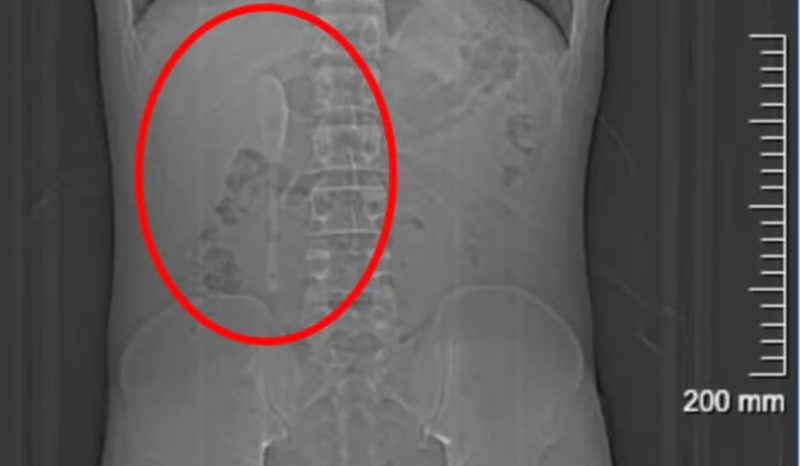

Durante os cinco meses seguintes, Yan seguiu com sua rotina normalmente, sem sintomas significativos, e até praticava exercícios físicos. Somente em junho, após desconfiar que havia ingerido algum pedaço de plástico com uma refeição de delivery, decidiu procurar atendimento médico em um hospital de Xangai. Para surpresa dos médicos e do próprio paciente, os exames revelaram que a colher estava alojada no duodeno – a primeira parte do intestino delgado.

Devido à posição delicada do objeto e à superfície lisa, a remoção apresentava riscos de perfuração, inflamação e hemorragia interna. A equipe médica optou por uma cirurgia endoscópica de alta complexidade, que durou cerca de nove horas. O procedimento envolveu o uso de dois tipos de pinças, permitindo que a colher fosse puxada de volta ao estômago e, posteriormente, removida com segurança.